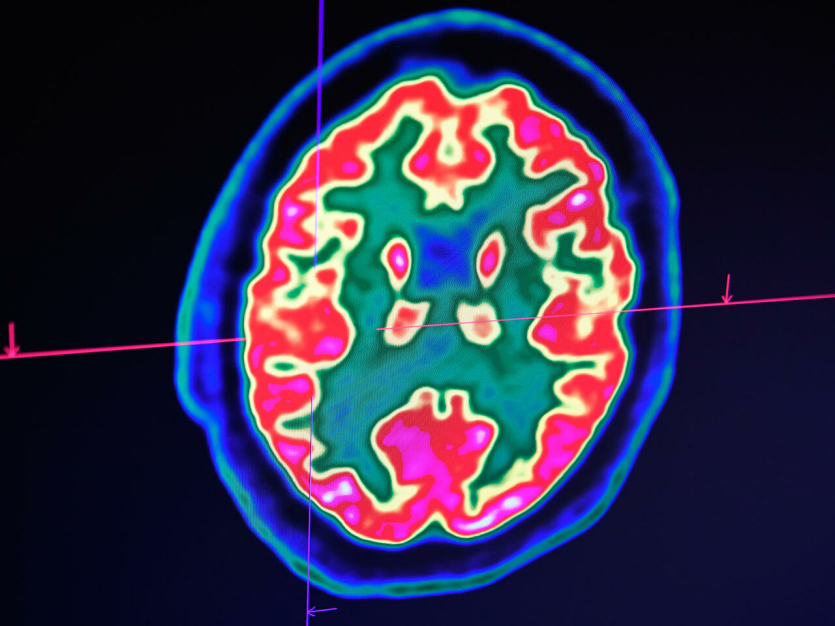

- La découverte récente d'un lien entre la sclérose en plaques et le virus d'Epstein-Barr fait espérer une meilleure riposte à terme face à cette maladie, soulignent des spécialistes de la sclérose en plaques avant la journée mondiale de cette maladie, aujourd'hui lundi. Les traitements, quiIl vous reste 84% de l'article à découvrir.Cet article est réservé aux abonnés.